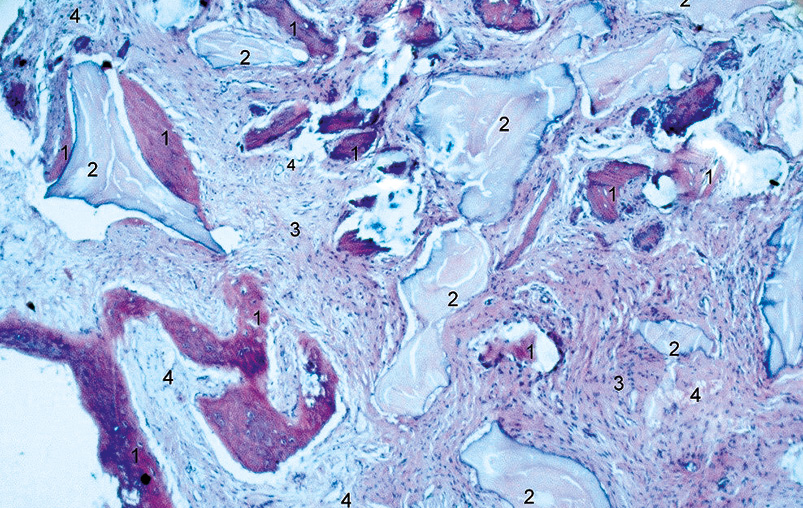

В результате морфологического исследования фрагмента костной ткани, полученного при раскрытии заглушки имплантата, на микропрепарате на границе гранулированного ксеногенного костнопластического материала и в соединительной ткани визуализировали явления остеогенеза (рис. 5).

Рис. 5. Фрагмент костного регенерата через 120 дней после трансплантации. 1 — новобразованная костная ткань, 2 — костнопластический материал, 3 — грубоволокнистая соединительная ткань, 4 — сосуды. Окраска гематоксилин-эозин. ×60.

Fig. 5. Fragment of bone regenerated 120 days after transplantation. 1-newly formed bone tissue, 2-bone graft, 3-coarse-fibrous connective tissue, 4-vessels. Hematoxylin-eosin stain, ×60.

В соединительнотканной строме наблюдается новообразованная ретикулофиброзная костная ткань с одновременной резорбцией костнопластического материала. Остеобласты с поверхности костных балок распространялись на остеопластический материал. Образование первичных остеогенных островков в соединительной ткани регенераторного типа, очаги естественной биодеградации трансплантата (рис. 6).

Большая часть поверхности материала окружена балками новообразованной костной ткани с активными остеобластами на поверхности, отложениями остеоида. Костные балки были представлены как ретикулофиброзной, так и пластинчатой костной тканью. Новообразованная костная ткань, располагающаяся на остеопластическом материале, плотно контактировала с костной тканью и остеоидом. Основные участки пролиферативной активности остеобластов обнаруживались на гранулах костнопластического материала. Гранулы костнопластического материала на своей поверхности имели многоядерные клетки, напоминающие остеокласты.